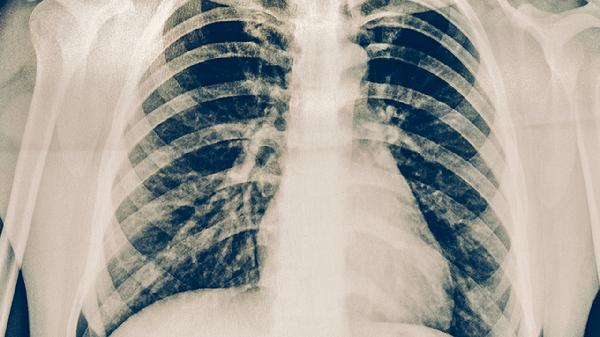

糖尿病、矽肺、慢性腎功能不全等疾病患者更易繼發(fā)肺結(jié)核。血糖控制不佳的糖尿病患者結(jié)核發(fā)病率顯著增高。這類患者需積極治療原發(fā)病,定期進(jìn)行胸部X線檢查。治療時需注意抗結(jié)核藥物與基礎(chǔ)疾病用藥的相互作用,如利福平膠囊可能減弱降糖藥效果。